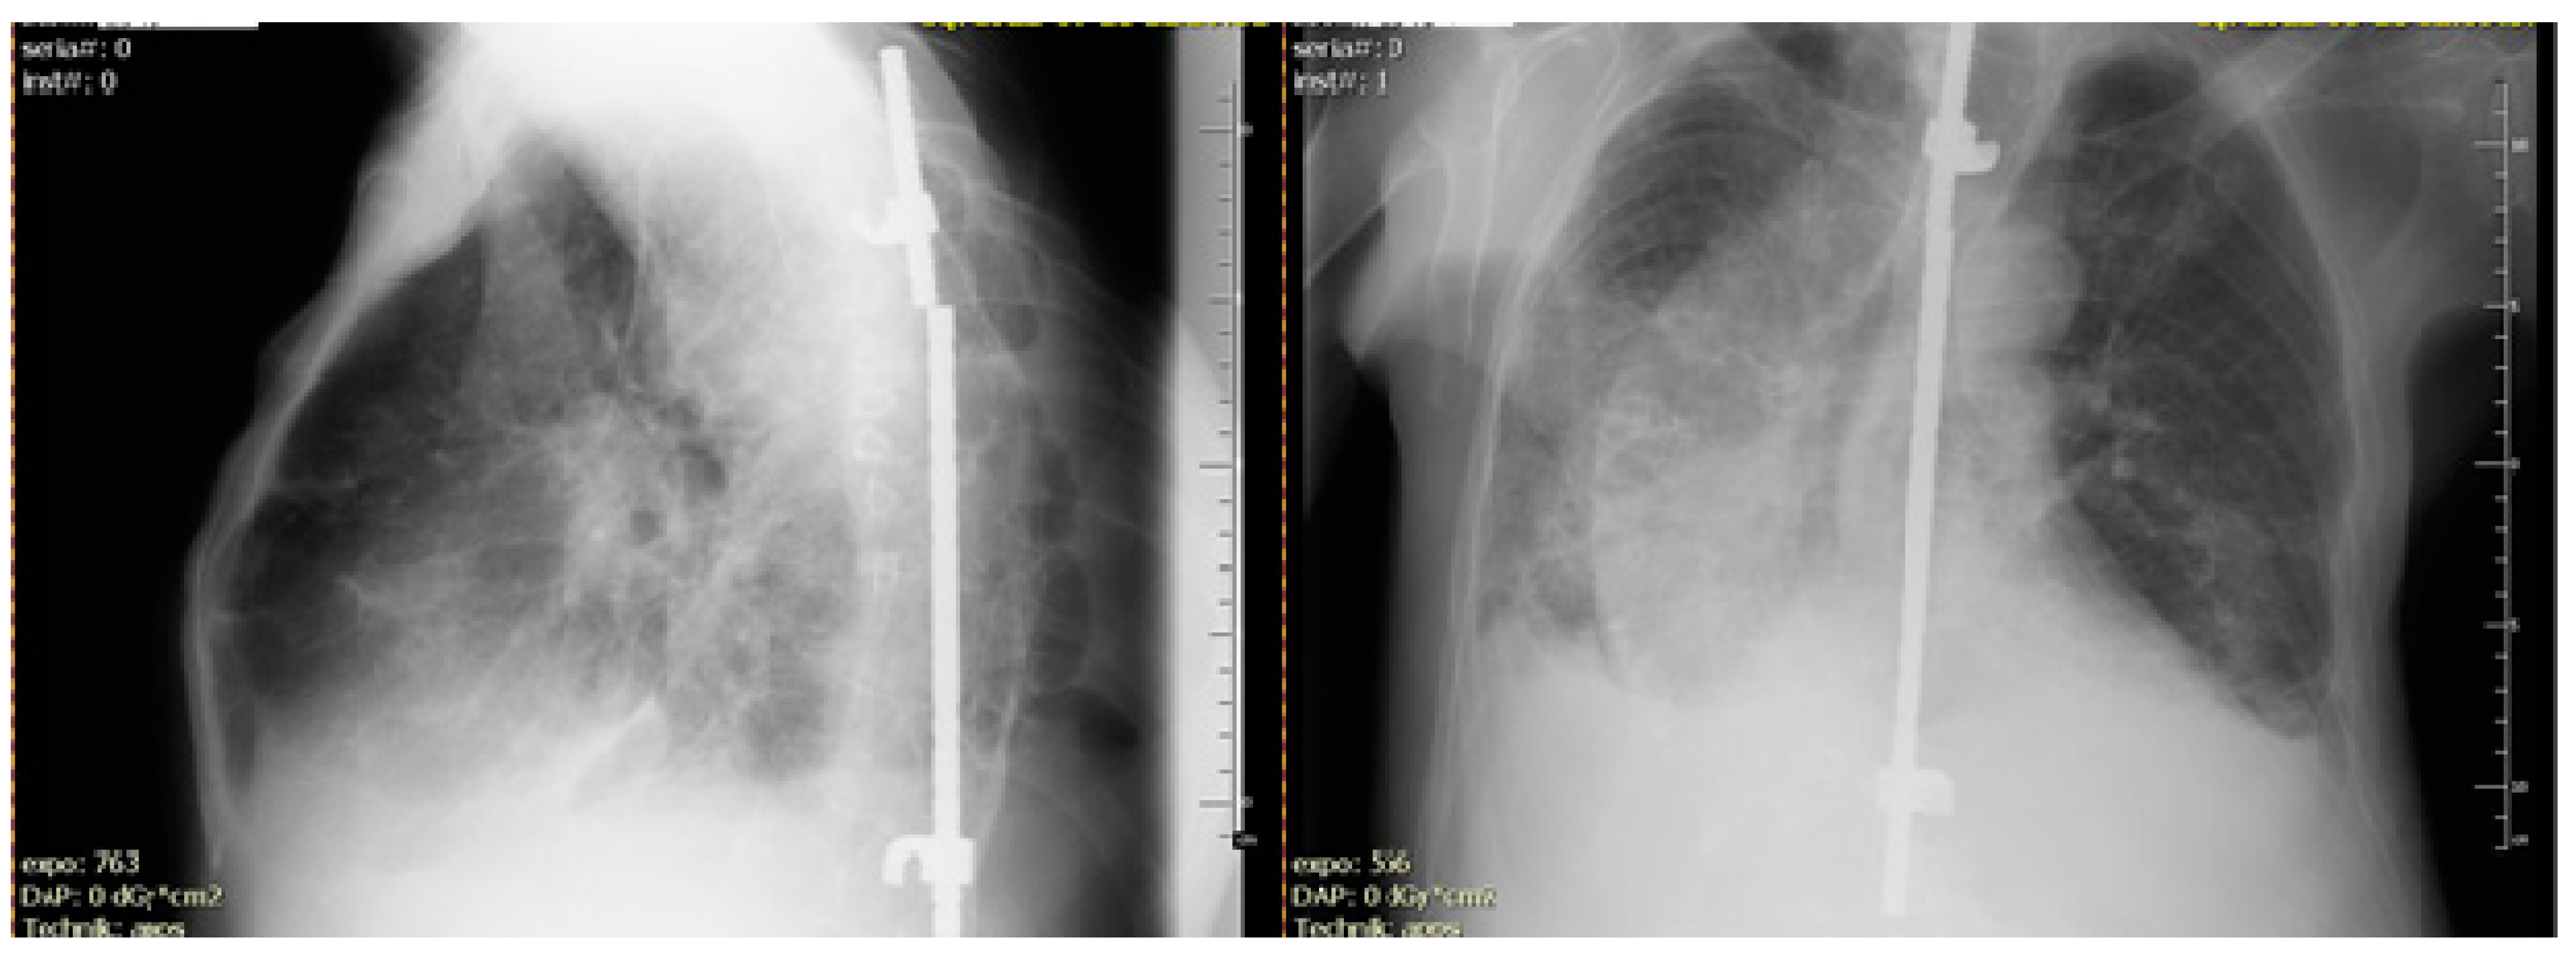

His medical history included ankylosing spondylitis (AS), rheumatoid arthritis (RA), and ventilation disorders caused by a significant deformation of the chest. Because of evidence of spinal instability (vertebral fracture) at the age of 14, he was treated with a spinal column stabiliser (Figure 1).

Figure 1.

X-ray examination during admission to the Department of Pulmonary Diseases. Overlapping post-inflammatory fibrosis and cavities were observed.

X-ray studies were repeated every year, mainly for a bone examination of his RA or post-medical osteoporosis (with the rheumatologic indication). The patient’s performance was constantly deteriorating. The X-ray alterations of an upper lobe of the lung were observed and interpreted by rheumatologist as a systemic manifestation of AS and nontuberculous fibrosis (probably an adverse drug reaction to the disease-modifying treatment of RA and AS).